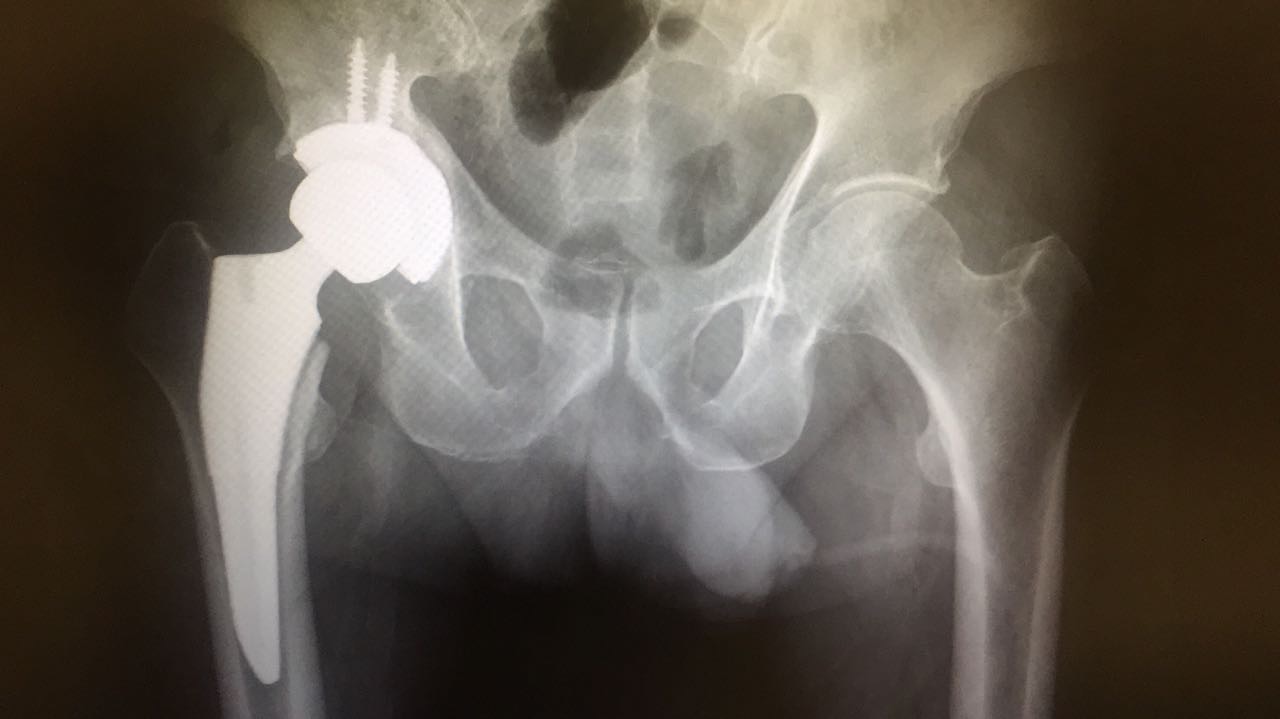

Prótesis de Cadera

Es una cirugía para reemplazar toda o parte de la articulación de la cadera con una articulación artificial (prótesis), con la intención de mejorar el dolor y la movilidad de la cadera.